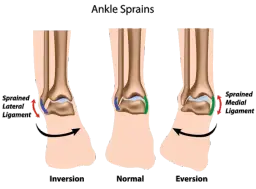

Różnice między skręceniem a zwichnięciem kostki

Skręcenie kostki to uraz, który występuje, gdy więzadła są nadmiernie rozciągnięte lub uszkodzone, podczas gdy zwichnięcie polega na przemieszczeniu kości w stawie. W przypadku skręcenia, objawy obejmują ból, obrzęk oraz ograniczenie ruchomości, ale kości pozostają na swoim miejscu. Z kolei zwichnięcie charakteryzuje się widoczną deformacją stawu i intensywnym bólem.- Skręcenie: ból, obrzęk, ograniczenie ruchomości, kości na swoim miejscu.

- Zwichnięcie: intensywny ból, deformacja stawu, przemieszczenie kości.

- Przyczyny: skręcenie często wynika z nieprawidłowego stawiania stopy, zwichnięcie może być efektem silnego uderzenia lub upadku.